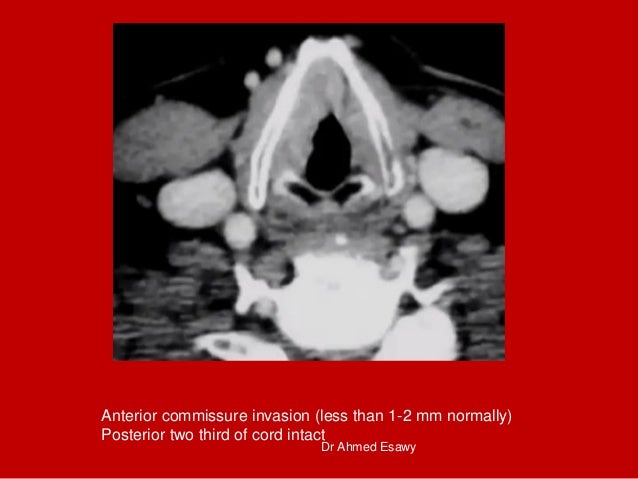

31. 31. Anterior commissure invasion (less than 1-2 mm normally) Posterior two third of cord intact Dr Ahmed Esawy

29. 29. Patterns of tumor invasion: • anterior extension into anterior commissure – >1 mm thickness of anterior commissure – invasion of contralateral vocal cord via anterior commissure • posterior extension to arytenoid cartilage, posterior commissure, cricoarytenoid joint • subglottic extension – tumor >5 mm inferior to level of vocal cords • deep lateral extension into paralaryngeal space • Prognosis:T1 carcinoma rarely metastasizes (2%) due to absence of lymphatics within true vocal cords Dr Ahmed Esawy